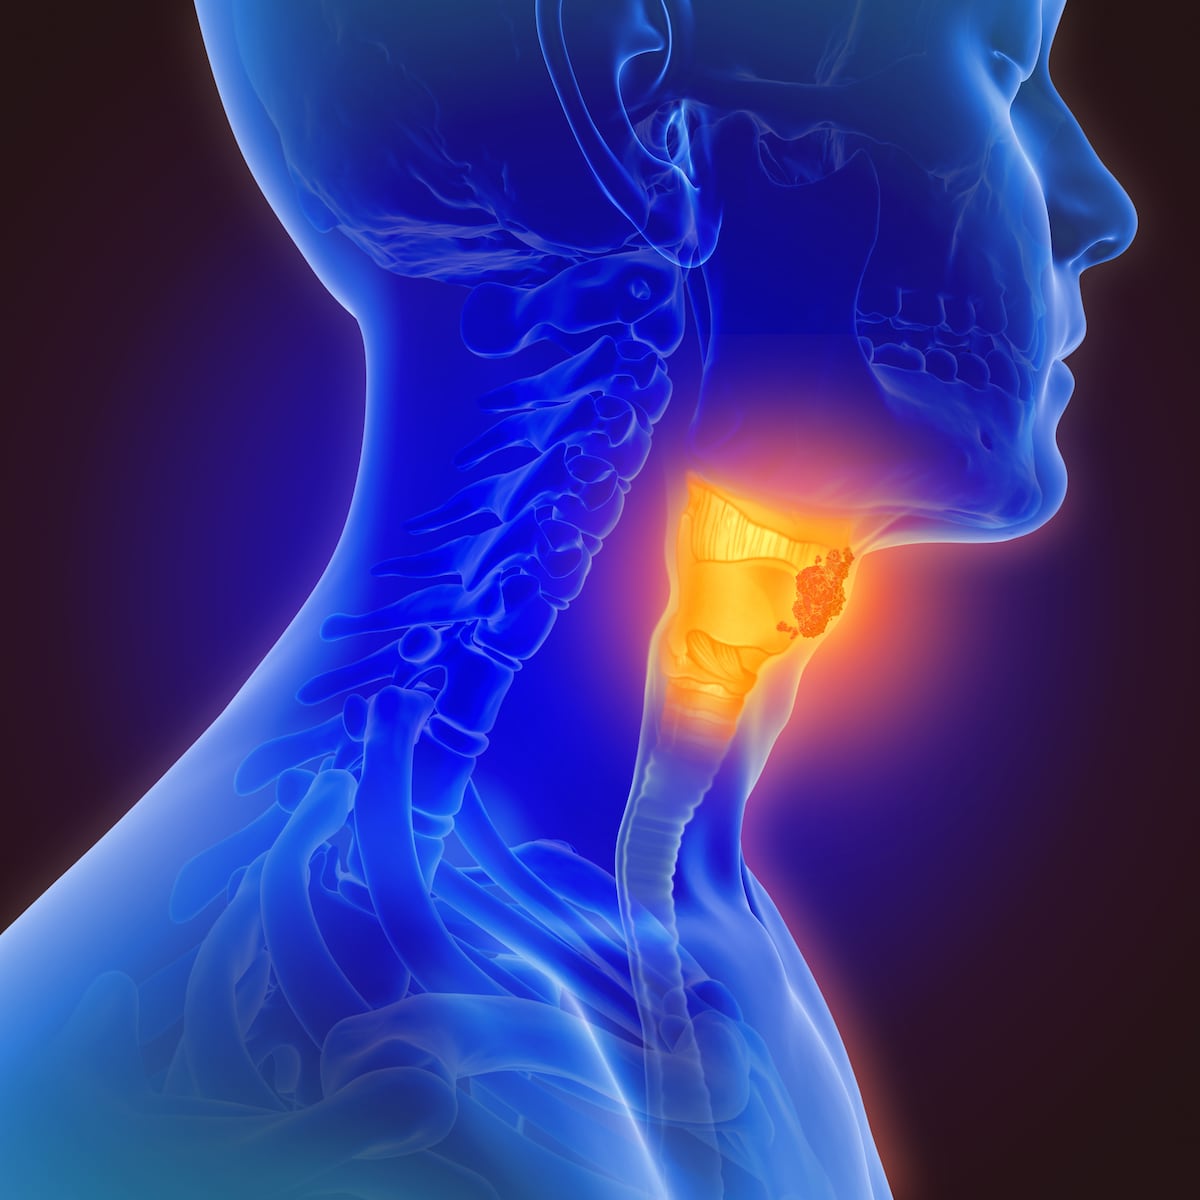

El cáncer de garganta es uno de los cánceres de más rápido crecimiento y a menudo está relacionado con el virus del papiloma humano (VPH). El cáncer de orofaringe, o cáncer de garganta, es un tipo de cáncer de cabeza y cuello que se puede dividir en dos subgrupos: cánceres asociados al VPH y cánceres no asociados al VPH. Y dependiendo del tipo del subgrupo, el tratamiento es diferente.

Throat cancer refers to cancer of the voice box, the vocal cords, and other parts of the throat, such as the tonsils and oropharynx. Throat cancer is often grouped into two categories: pharyngeal cancer and laryngeal cancer.

El consumo de tabaco y alcohol aumenta el riesgo de tumores no asociados al VPH, mientras que el VPH representa aproximadamente el 70% de los cánceres de cabeza y cuello.

“Lo que importa de todo eso es que tienen una biología diferente y son mucho más tratables, lo que significa que responden mejor a los tratamientos y tienden a tener una tasa de curación más alta. Estamos tratando estos tipos de cáncer de manera diferente a como tratamos algunos de los cánceres no asociados al VPH”, dice la Dra. Price.

Cirugía, radioterapia y quimioterapia son todas opciones de tratamiento, pero la Dra. Price advierte que es mejor reducir los riesgos de infección. “Las tres grandes maneras: no fumar tabaco, disminuir el consumo de alcohol y, por fin, vacunarse contra el VPH”, dice.

“Sabemos que fumar y el consumo de alcohol son grandes factores de riesgo para el cáncer de cabeza y cuello, especialmente si hace ambos. Eso aumenta aún más su riesgo”, advierte la Dra. Price.

Y ella fomenta una dieta saludable. “De hecho, deberíamos esforzarnos por tener una buena dieta de alimentos integrales, tratando de minimizar la ingesta de alimentos procesados y azúcares refinados”, dice la Dra. Price.